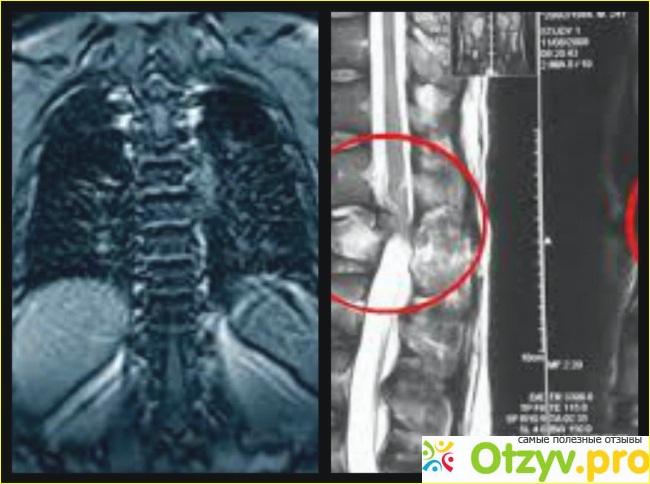

У меня появились боли в груди, которые усиливались, а также я начала кашлять. Участковый врач пытался списать это на какое то инфекционное заболевание или осложнение от простуды. Но простудой последний раз я болела очень давно, а наличие инфекции в организме не подтвердилось. Я уже и не знала, на что думать. В голову лезли самые страшные диагнозы. Врач посоветовал мне сделать МРТ грудного отдела позвоночника. Я хоть и понимала, что это для меня дорогая процедура, но здоровье и желание понять, что со мной, было намного дороже. Я записалась в одну из клиник на МРТ. Врач в клинике подробно проконсультировал меня о том, как будет все проходить. МРТ это сродни тому же рентгену, но дает более точный результат. Также врач предположил, что вполне возможно, что основной причиной моего недомогания, вполне может явиться проблема с позвоночником в грудном отделе.

Хотя с этой проблемой обращаются не так часто, как например, с проблемами с позвоночником в шейном и поясничном отделе, но все равно, не стоит исключать того, что проблема кроется именно в этом. Я ознакомилась с памяткой. В ней говорилось о самой процедуре, подготовке к ней и о том, что может показать МРТ. МРТ в первую очередь направлено на обследование спинномозгового канала на уровне груди. С его помощью можно увидеть различные опухоли, как доброкачественные так и злокачественные. Можно таким образом распознать и рассеянный склероз. Можно разглядеть и дистрофию позвоночника, оказывается даже такое бывает.

Можно понять нет ли проблем с сосудами в этой области. Что, кстати, может быть причиной моего плохого самочувствия. Этого нельзя разглядеть на рентгене, поэтому все чаще, для постановки более точного диагноза, назначают именно МРТ. И хоть это тоже вредно для организма, но не более, чем сам рентген.